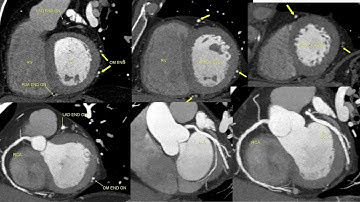

Comprehensive Cardiac of Philips workstations with a triple rule out protocol